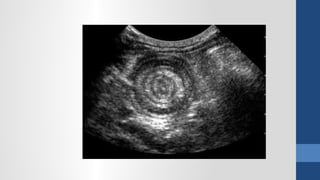

2. Ch n đoán hình nhẩ ả

Siêu âm

2. Ch nđoán hình nhẩ ả Siêu âm Xquang b ng đ ng không chu n bụ ứ ẩ ị CT Scanner N i soi thăm dòộ

• #64 Xquang - Viêm phổi (thâm nhiễm phổi), - Tắc ruột (mức nước hơi), - Thủng tạng rỗng (hơi tự do trong bụng), - Sỏi thận và hệ niệu (vôi hóa bất thường), - Viêm RT (fecalith)?, - Thoát vị kẹt (ruột trồi khỏi giới hạn ổ bụng)?, - Nhồi máu mạc treo (hơi trong TM cửa), - Viêm tụy mãn (vôi hóa tụy), - Viêm tụy cấp (sentinel loop, colon cutoff), - Phình ĐM (bờ vôi hóa)?, - Tụ máu hoặc áp xe sau phúc mạc (mất bóng cơ psoas), Siêu âm - Những bệnh vùng chậu (u buồng trứng, Viêm RT cấp, thai ngoài tử cung, thai trong tử cung), - Sỏi mật (túi mật, đường mật), - Gan (áp xe, bướu gan), - Thận (ứ nước, sỏi), - Dịch tự do trong bụng (xuất huyết nội, dịch viêm, ascites) CT Scan: - có giá trị định bệnh cao hơn SA nhưng không nên dùng cho BN nữ đang mang thai hoặc cho trẻ em. - Viêm đại tràng thiếu máu (dấu ấn ngón tay trên thành đại tràng). &amp;lt;number&amp;gt;